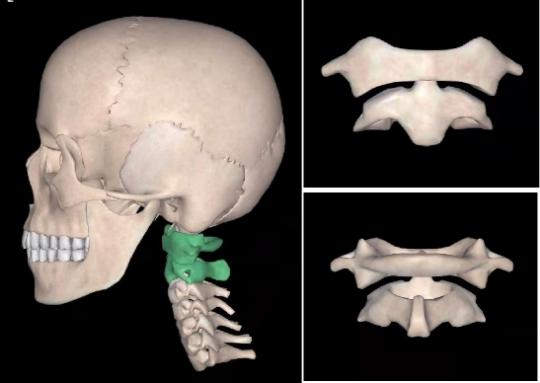

4)寰(huan,二声)枢关节:上颈椎痛伴活动受限,RA需排查!

RA是一种以慢性滑膜炎和侵袭性关节炎为特征的自身免疫病,本病可进行性侵蚀和破坏关节,从而导致关节畸形及功能丧失。临床上我们更多关注的是双手、双足小关节的病变,而对颈椎(尤其是寰枢关节)受累的重视程度却远远不够。

RA患者双手、双足小关节骨侵蚀破坏严重的患者,且颈椎活动受限、上颈椎(压)痛的患者,更易出现寰枢关节受累,应及时进行寰枢关节的CT和(或)核磁共振(MRI)检查,尤其MRI检查在RA伴寰枢关节受累的早期诊断中发挥重要作用。